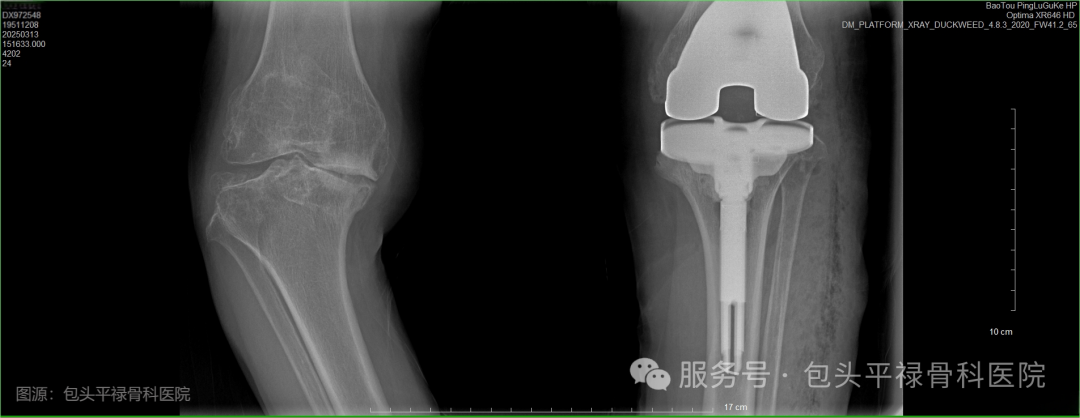

顾名思义,是指通过手术将受损的膝关节部分或全部替换为人工关节,以恢复关节功能、缓解疼痛和改善生活质量。医生会移除严重磨损的关节部位,在原位安装上与原始膝关节表面形状类似的假体,使用骨水泥使假体与患者自身的股骨和胫骨固定在一起,从而恢复膝关节的正常功能。